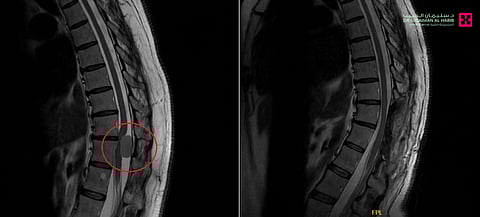

وأوضح أن المريضة وصلت للعيادة على كرسي متحرّك غير قادرة على الحركة نهائياً ، أو أداء مهامها اليومية الاعتيادية، نتيجة التأخر في التشخيص والعلاج، حيث تمّ إجراء الفحص السريري الذي أثبت أن تلك الأعراض تتعلق بأورام الحبل الشوكي، وعليه تم إخضاعها لفحوصات بالرنين المغناطيسي (M.R.I).

وقال د. النبهان؛ إن نتائج الفحوصات أبانت بدقة وجود ورم كبير في الفقرات الصدرية بالعمود الفقري بطول 3 سم، وضاغط بشدة على النخاع الشوكي مسبّباً الأعراض السابق ذكرها، الأمر الذي استدعى التدخل الجراحي العاجل، مشيراً إلى أنه عقب دراسة الفريق الطبي لنتائج الفحوصات، تمّ إطلاع المريضة على الخطة العلاجية.

ووصف د. النبهان؛ حالة المريضة بأنها تُعد من الحالات المعقدة وعالية الخطورة، نظراً لكبر حجم الورم وموقعه الدقيق، علاوة على إمكانية حدوث نزيف عقب استئصال الورم أو تأثر الأعصاب المحيطة به، مؤكداً أن الفريق الطبي قام بدراسة كافة تلك المعلومات، قبل إجراء العملية التي تم فيها استخدام المجهر الإلكتروني المتطور من النوع "PENTERO"، حيث تحرير الورم من الالتصاقات واستئصاله بصورة كاملة دون حدوث أي مضاعفات ولله الحمد.